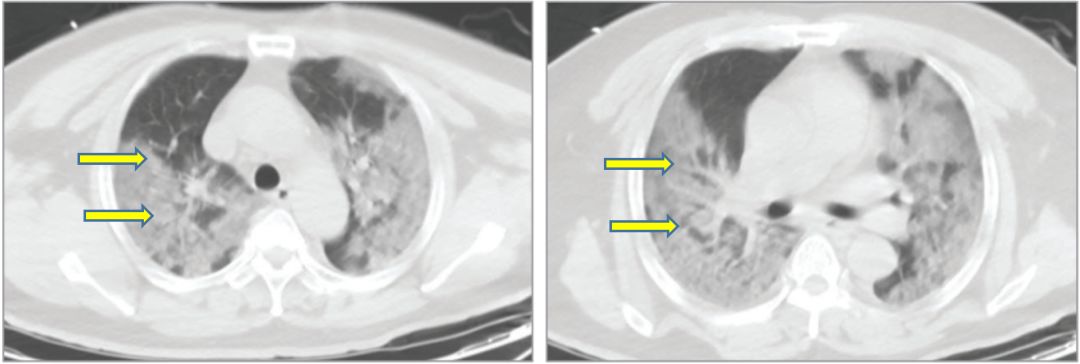

2019新型冠状病毒(2019-nCoV)肺炎患者的

1262x630 - 136KB - JPEG